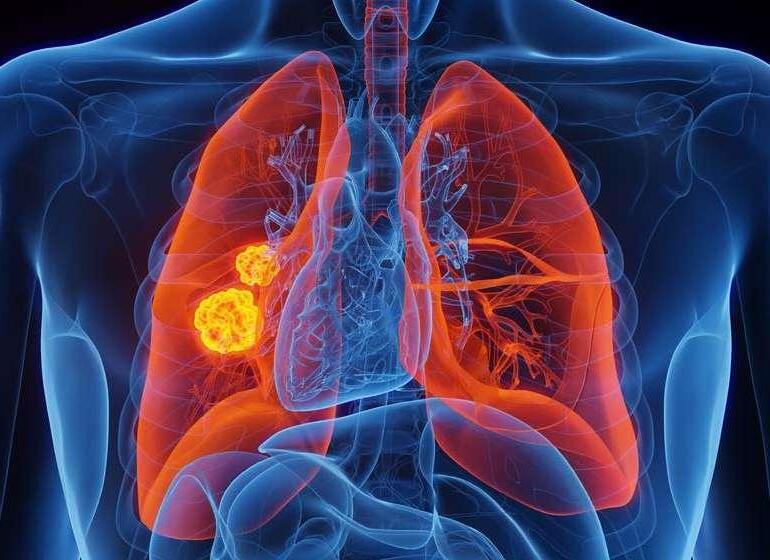

CÁNCER DE PULMÓN

EL CÁNCER DE PULMÓN ES UNA ENFERMEDAD QUE PUEDE AFECTAR A CUALQUIERA, INDEPENDIENTEMENTE DEL GÉNERO, LA EDAD O EL HISTORIAL DE TABAQUISMO. Para nuestros pacientes y sus seres queridos, es fundamental entender los signos y síntomas del cáncer de pulmón, así como las opciones de detección temprana. La información es poder, y en conmemoración del Día Mundial del Cáncer de Pulmón (17 de noviembre), proporcionamos una guía completa sobre este tema vital.

SÍNTOMAS DE ALERTA: Los síntomas pueden variar, pero algunos signos comunes incluyen una tos persistente que no mejora con el tiempo, expectoración con sangre, dificultad para respirar incluso en reposo y dolor en el pecho, hombros o espalda baja. Otros indicadores incluyen cambios en la voz, fatiga extrema que no mejora con el descanso y pérdida de peso inexplicada. Si experimenta cualquiera de estos síntomas, es esencial consultar a un médico para una evaluación detallada.

CAUSAS Y FACTORES DE RIESGO: El tabaquismo sigue siendo la causa principal del cáncer de pulmón. Fumar cigarrillos, cigarros electrónicos y pipas aumenta significativamente el riesgo. Además, la exposición prolongada al humo de segunda mano puede ser perjudicial. Otras causas incluyen la exposición ocupacional a carcinógenos como el asbesto y el radón, así como antecedentes familiares de la enfermedad y ciertas enfermedades pulmonares crónicas, como la EPOC.

La prevención del cáncer de pulmón comienza con el abandono del tabaquismo y evitar el humo de segunda mano.

PREVENCIÓN Y DETECCIÓN TEMPRANA: La prevención del cáncer de pulmón comienza con el abandono del tabaquismo y evitar el humo de segunda mano. Para aquellos con alto riesgo, como los fumadores y exfumadores, los exámenes de detección como la tomografía computarizada de baja dosis son herramientas efectivas para identificar anomalías pulmonares en etapas tempranas cuando el tratamiento es más efectivo. Adoptar un estilo de vida saludable, que incluya una dieta equilibrada y actividad física regular, también puede reducir el riesgo de desarrollar cáncer de pulmón y mejorar la salud pulmonar en general.

En este Día Mundial del Cáncer de Pulmón, queremos enfatizar la importancia de la concientización y el apoyo. La educación pública sobre los riesgos y síntomas puede ayudar a las personas a tomar medidas preventivas y a buscar atención médica temprana si es necesario. Además, brindar apoyo emocional y psicológico a los pacientes y sus familias es esencial para ayudarles a sobrellevar los desafíos del diagnóstico y el tratamiento del cáncer de pulmón.

El cáncer de pulmón es una enfermedad seria pero tratable, especialmente si se detecta en sus etapas iniciales. La clave está en la prevención, la detección temprana y el apoyo continuo. Estamos aquí para ustedes, nuestros valiosos pacientes, para proporcionar información, apoyo y atención compasiva en cada paso del camino. Juntos, podemos enfrentar el cáncer de pulmón y trabajar hacia un futuro más saludable y esperanzador para todos.